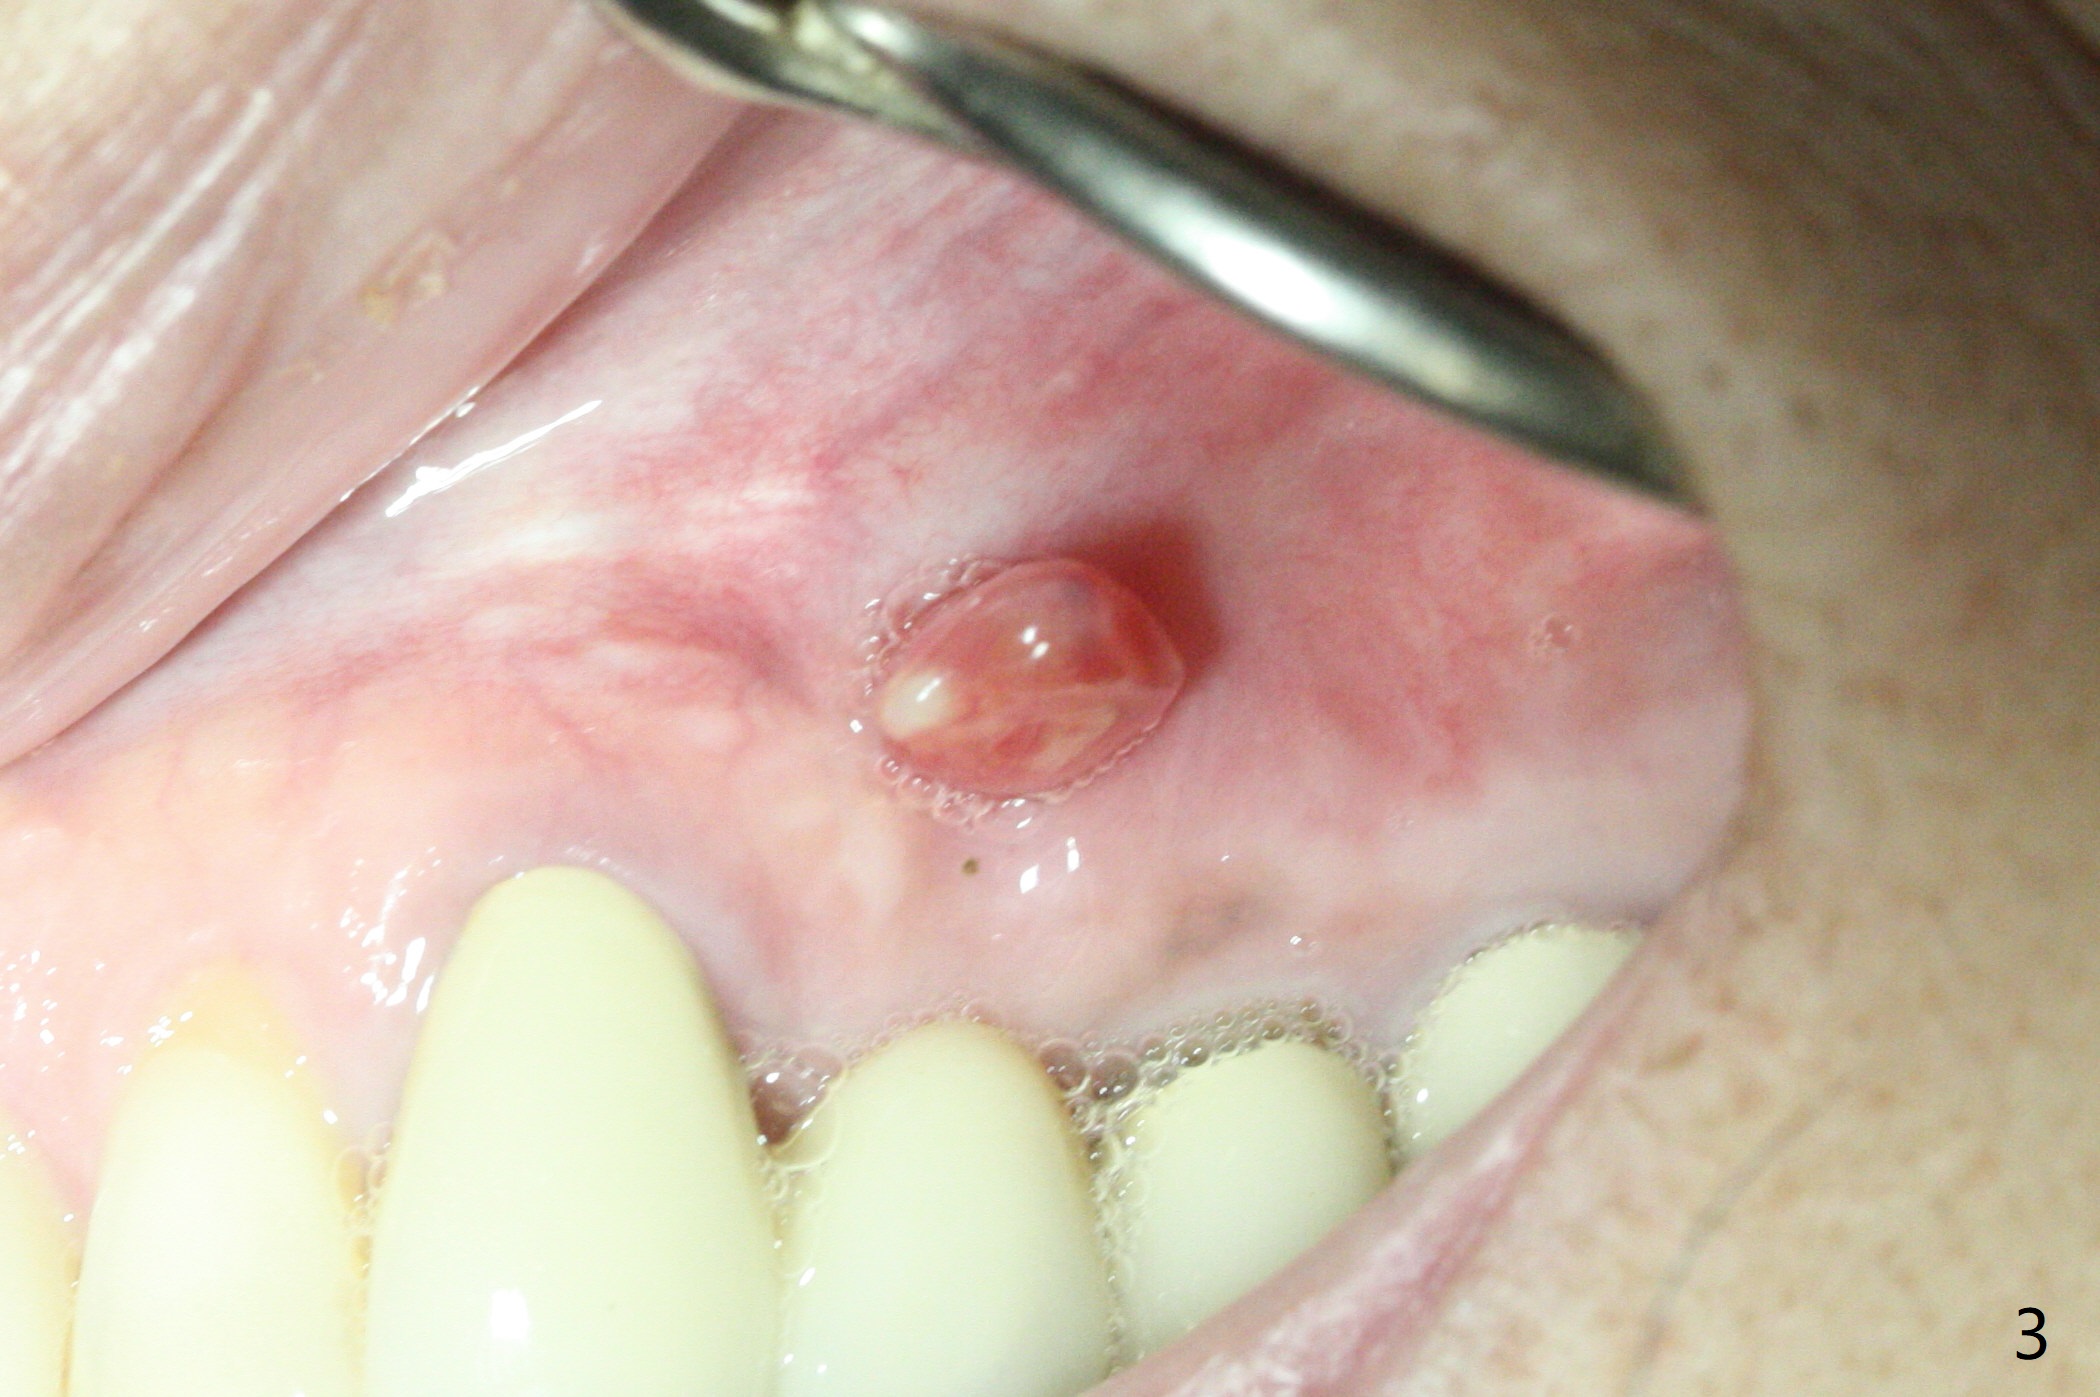

A 73-year-old woman has had discomfort with the upper left FPD for long time (Fig.1). A large asymptomatic fistula is found recently above the pontic with a small superior pedicle (Fig.2,3 <). CT shows radiopaque (Fig.1,4 *) and radiolucent (Fig.4 >) lesions are associated with the tooth #13, instead of the tooth #11.